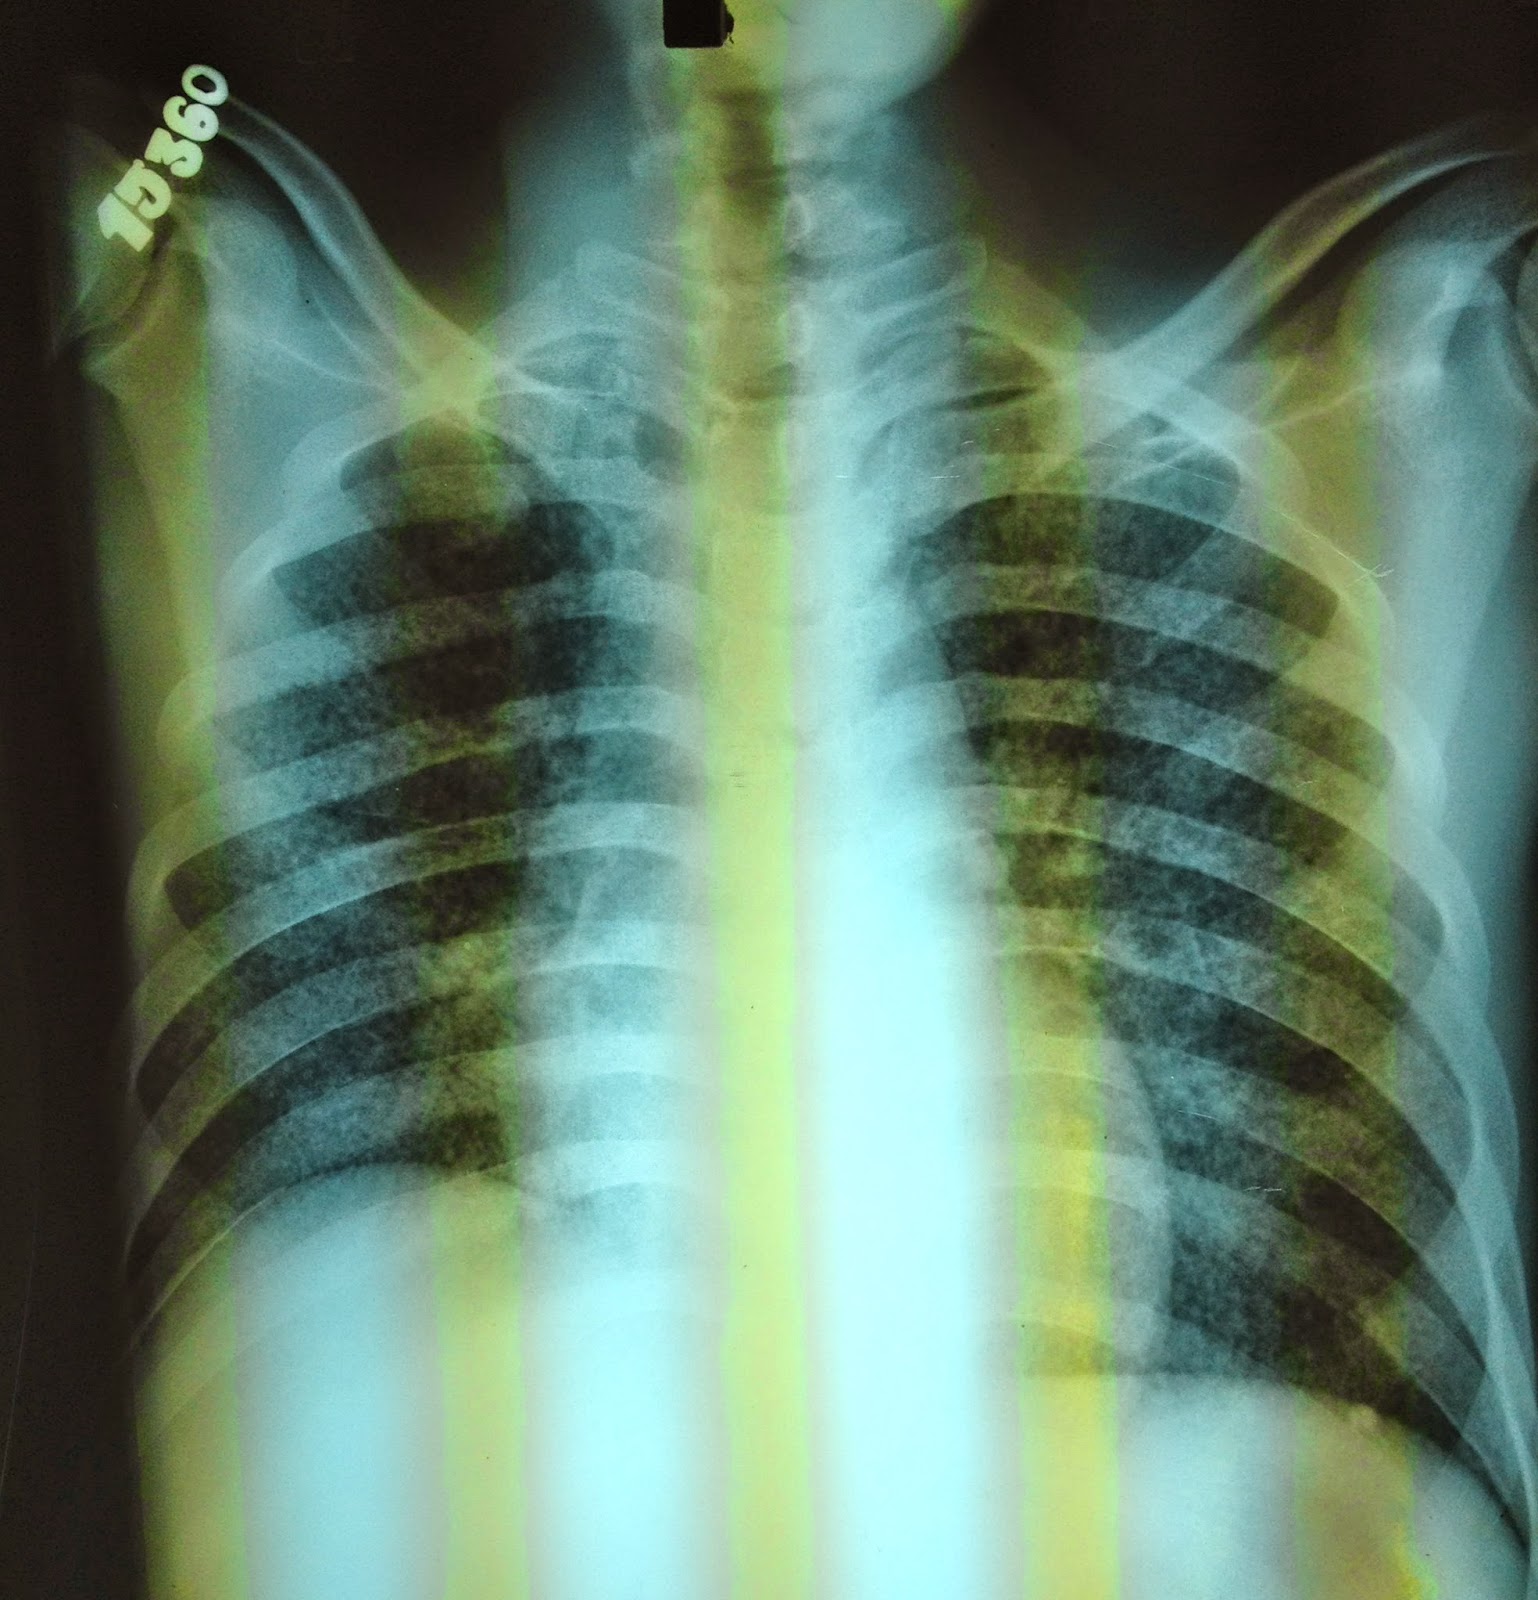

Chest X-ray of a person with advanced tuberculosis. Diagnosis of active TB relies on radiology. Doctors often look at an X-ray of the chest. In addition, they check body fluids. These fluids have microbes in them, which are grown in cell cultures. ... Read Article

DIAGNOSIS AND EVALUATION OF ACTIVE TUBERCULOSIS (TB) DISEASE the chest x-ray may be suggestive of TB but cannot be used solely to make a final diagnosis. Serial chest x-rays may be used to judge resolution of pulmonary TB. ... Read Document